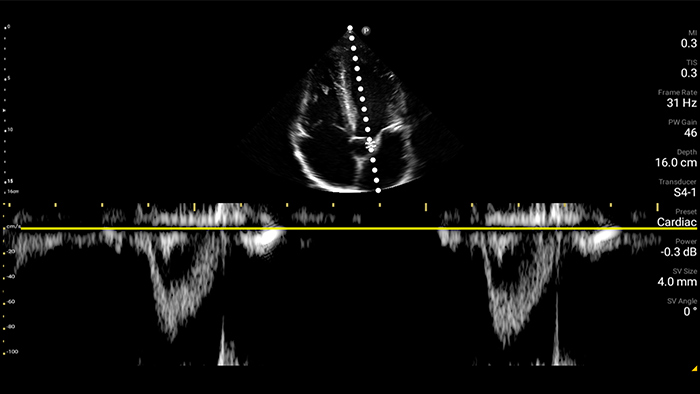

Lumify handheld ultrasound offers images that enhance diagnostic confidence.

See more when it counts

Lumify can help you make real-time decisions with more confidence, from assessment to recovery. Reveal the subtle details of an image, uncover enriched tissue definition with multiple angles and much more.